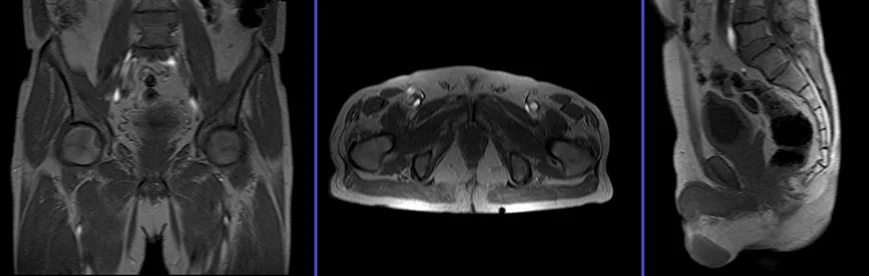

T2 tse sagittal 3mm SFOV

Plan the sagittal slices on the axial plane; angle the positioning block parallel to the interpubic fibrocartilage and the anal canal. Check the positioning block in the other two planes. Provide an appropriate angle in the coronal plane (parallel to the rectum and the anal canal). Ensure that the slices are sufficient to cover the entire pelvis from the right acetabulum to the left acetabulum. The field of view (FOV) must be large enough to encompass the entire pelvis (usually 270mm-300mm). To reduce artifacts caused by arterial pulsation and breathing, consider adding saturation bands on top and in front of the sagittal block.

T2 tse axial 5mm big FOV

Plan the large FOV axial slices on the coronal plane. Angle the positioning block parallel to the right and left hip joints. Check the positioning block in the other two planes, ensuring an appropriate angle is given in the sagittal plane (horizontally across the pelvis). The slices must be sufficient to cover the entire pelvis from the iliac crest down to 1 inch below the symphysis pubis. The FOV should be large enough to encompass the whole pelvis, typically ranging from 350mm to 400mm. To reduce artifacts from arterial pulsation, peristalsis, and breathing, consider adding saturation bands on top of the axial block.

T2 tse axial oblique 3mm SFOV

Plan the axial oblique slices on the sagittal plane. Align the position block perpendicular to the rectum, taking care to position the axial slice precisely perpendicular to any visible cancer within the rectum. Verify the positioning block’s alignment in the other two planes. Ensure an appropriate angle in the coronal plane, also perpendicular to the rectal cancer. Adjust the number of slices to cover the entire rectal cancer adequately. To minimize artifacts caused by arterial pulsation, peristalsis, and breathing, consider adding saturation bands on top and anterior to the axial block.

T2 tse coronal oblique 3mm SFOV

Plan the coronal oblique slices on the sagittal plane and angle the positioning block parallel to the rectum. It is essential to align the coronal slice parallel to any visible cancer within the rectum. Check the positioning block in the other two planes. In the axial plane, ensure an appropriate angle is given either horizontally across the rectal cancer or parallel to the right and left hip joint. The slices must be sufficient to cover the entire rectum and pre-sacral space from the symphysis pubis up to the sacrum, as it is crucial to include the lymph nodes in the pre-sacral space. To reduce artifacts from arterial pulsation, peristalsis, and breathing, consider adding saturation bands on top and in front of the coronal block.